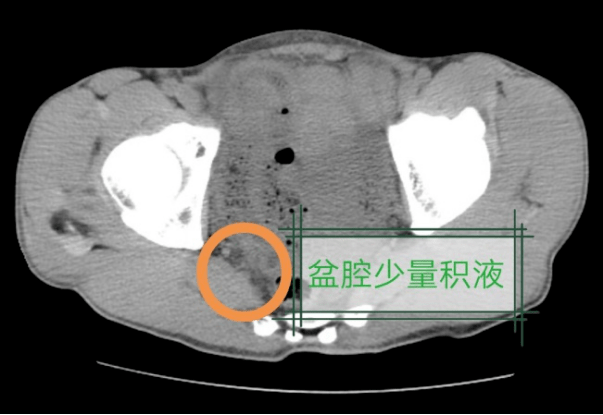

需立即住院治疗不排除少量出血黄先生下腹,盆腔少量积液医生通过急诊

上腹部疼痛,但超声只发现盆腔积液,怎么考虑?